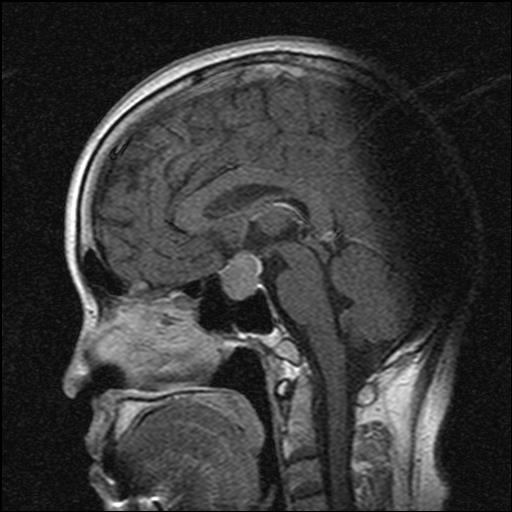

После пятидневной отмены левотироксина натрия зафиксировано снижение свободных фракций Т3 и Т4 до референсных значений, в то время как содержание ТТГ увеличилось с 17,5 до 35,6 мМЕ/л (0,25–3,5 мМЕ/л). При МРТ гипофиза с контрастированием верифицирована макроаденома гипофиза (20 × 25 × 15 мм) с супра-, пара-, инфраселлярным распространением (рис. 1). Пациентка осмотрена офтальмологом: данных за хиазмальный синдром не получено. Дополнительно было проведено УЗИ щитовидной железы: объем железы 9 см3 с эхографическими признаками аутоиммунного поражения.

Рис. 1. МРТ гипофиза: а – макроаденома гипофиза, сагиттальный срез; б – макроаденома гипофиза, фронтальный срез.